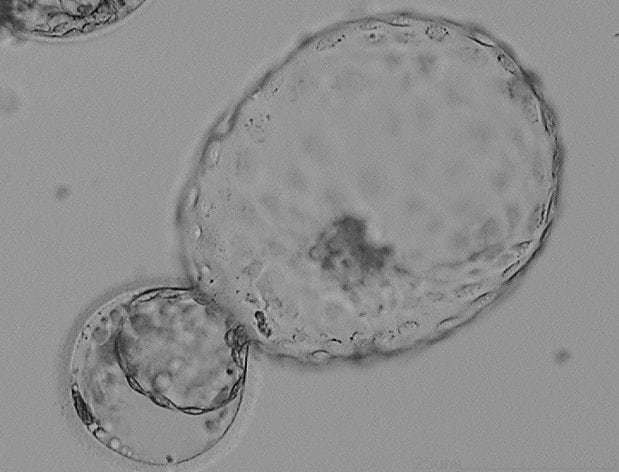

Picture 2 - the embryo hatches and is ready to implant

Picture 3 - shows an embryo which has been hatched using a laser